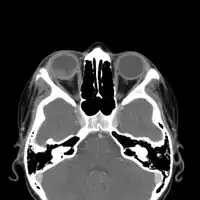

CT-scan head: Intraorbital enhancing mass lesion and two outer eyelid lesions with necrotic center and enhancing borders.